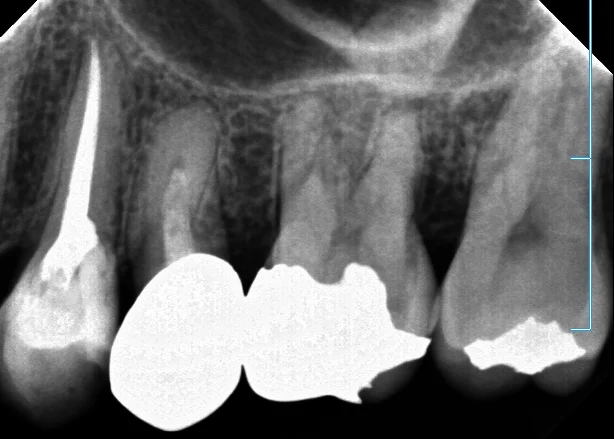

詰めたレントゲンがこちら。

実は途中で根の管が分岐していて・・・それでいてイスムスがあったので、その分岐した根管を更に削って大きな一本の根にしました。

イスムスというのは二つの根の間にある狭い交通路のようなもので、これが細菌繁殖の原因にもなりかねない危険なものです。

太さは0.1mmも無いので、よく見逃されていますが、その結果根の先に膿が溜まってしまいます。

術前術後がこちらですね。

根の先まで隙間なくしっかりと詰まっていて、最初のちょろっとしか入っていなかった薬に比べると随分としっかりと入ったのが分かると思います。